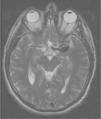

Aportamos el caso de un varón de 39 años, sin antecedentes de interés, que presentaba desde hacía dos meses cefalea frontal izquierda de carácter opresivo, recalcitrante a múltiples tratamientos y que se acompañaba de afectación retroocular homolateral, siendo el resto de la exploración neurológica normal. En la resonancia magnética nuclear se halló un aneurisma fusiforme gigante en la arteria cerebral media (fig. 1), por lo que se decidió realizar la embolización del mismo mediante un coil (espiral de platino) desprendible de Guglielmi tridimensional (Matrix2). El procedimiento angiográfico se llevó a cabo mediante dos sesiones separadas por 5 días, realizándose 12 series de imágenes de sustracción digital en la primera sesión y 20 en la segunda. El tiempo de fluoroscopia total fue de 90–100 minutos y la dosis total aproximada fue de 3Gy. Los principales planos utilizados fueron postero-anterior y oblicuo izquierdo-derecho. Al finalizar todo el procedimiento se consiguió formar un coágulo alrededor de la espiral que bloqueó la luz del aneurisma (figs. 2 y 3). El paciente mejoró de la cefalea, pero dos semanas más tarde acudió a la consulta de Dermatología por una placa de alopecia rectangular parieto-occipital izquierda sin signos de inflamación (fig. 4). No se observaron pelos en signos de exclamación y la maniobra de pilo-tracción fue intensamente positiva. El paciente evolucionó hacia una alopecia completa en dicha zona. Los pulsos arteriales superficiales bilaterales estaban conservados y los parámetros analíticos fueron estrictamente normales. Al estar localizada la placa en la zona de máxima radiación se relacionó con el procedimiento endovascular, por lo que no se pautó tratamiento y se citó mensualmente al paciente para comprobar la evolución. A los 5 meses se obtuvo la repoblación completa.